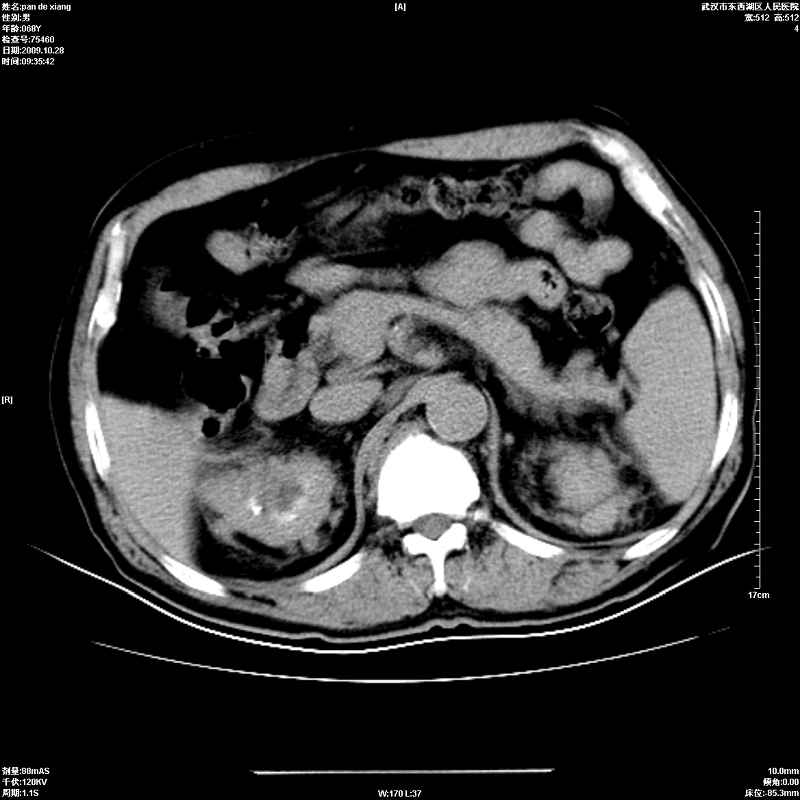

以下是引用杀毒软件在2009-10-28 20:41:00的发言:[br]结合临床考虑---白血病双肾改变或淋巴瘤。

以下是引用zxl51642在2009-10-29 9:59:00的发言:[br]结合临床“单克隆免疫球蛋白血症”,考虑双肾为继发损害并肾功能不全(尿中大量igg及少量iga、igm等大分子免疫球蛋白滤出所致继发损害),椎前软组织肿块为髓外造血。与浆细胞瘤有区别,平扫时有战友说的很清楚。